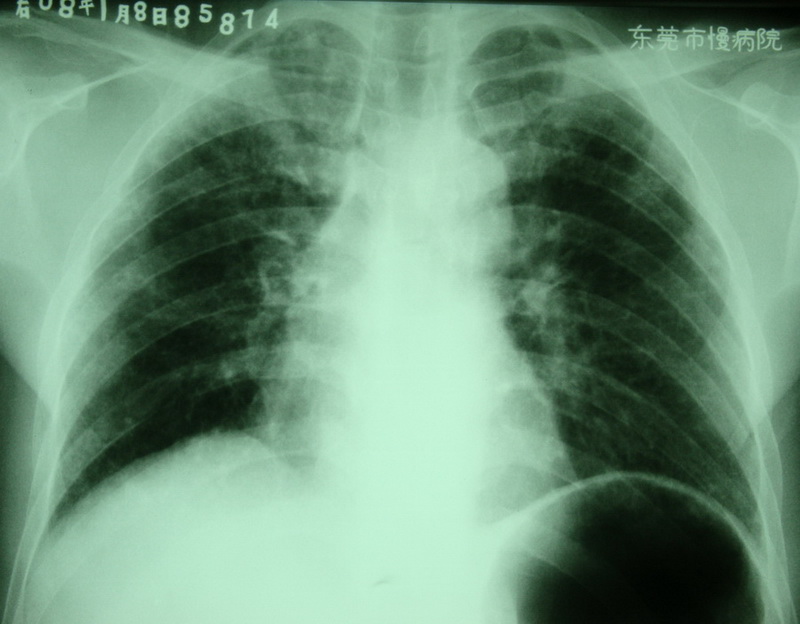

按顺序依次是:(都有粉尘职业史)

曾某,男,39岁,ii+尘肺,合并肺tb?